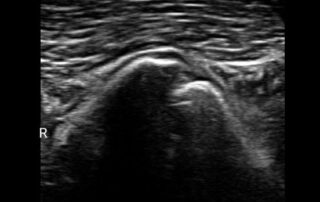

Umfangsvermehrungen am Kopf, aber auch Weichteile oder Fistelkanäle und das Zungenbein lassen sich im Ultraschall darstellen. Einziger Nachteil: Das Fell muss geschoren werden